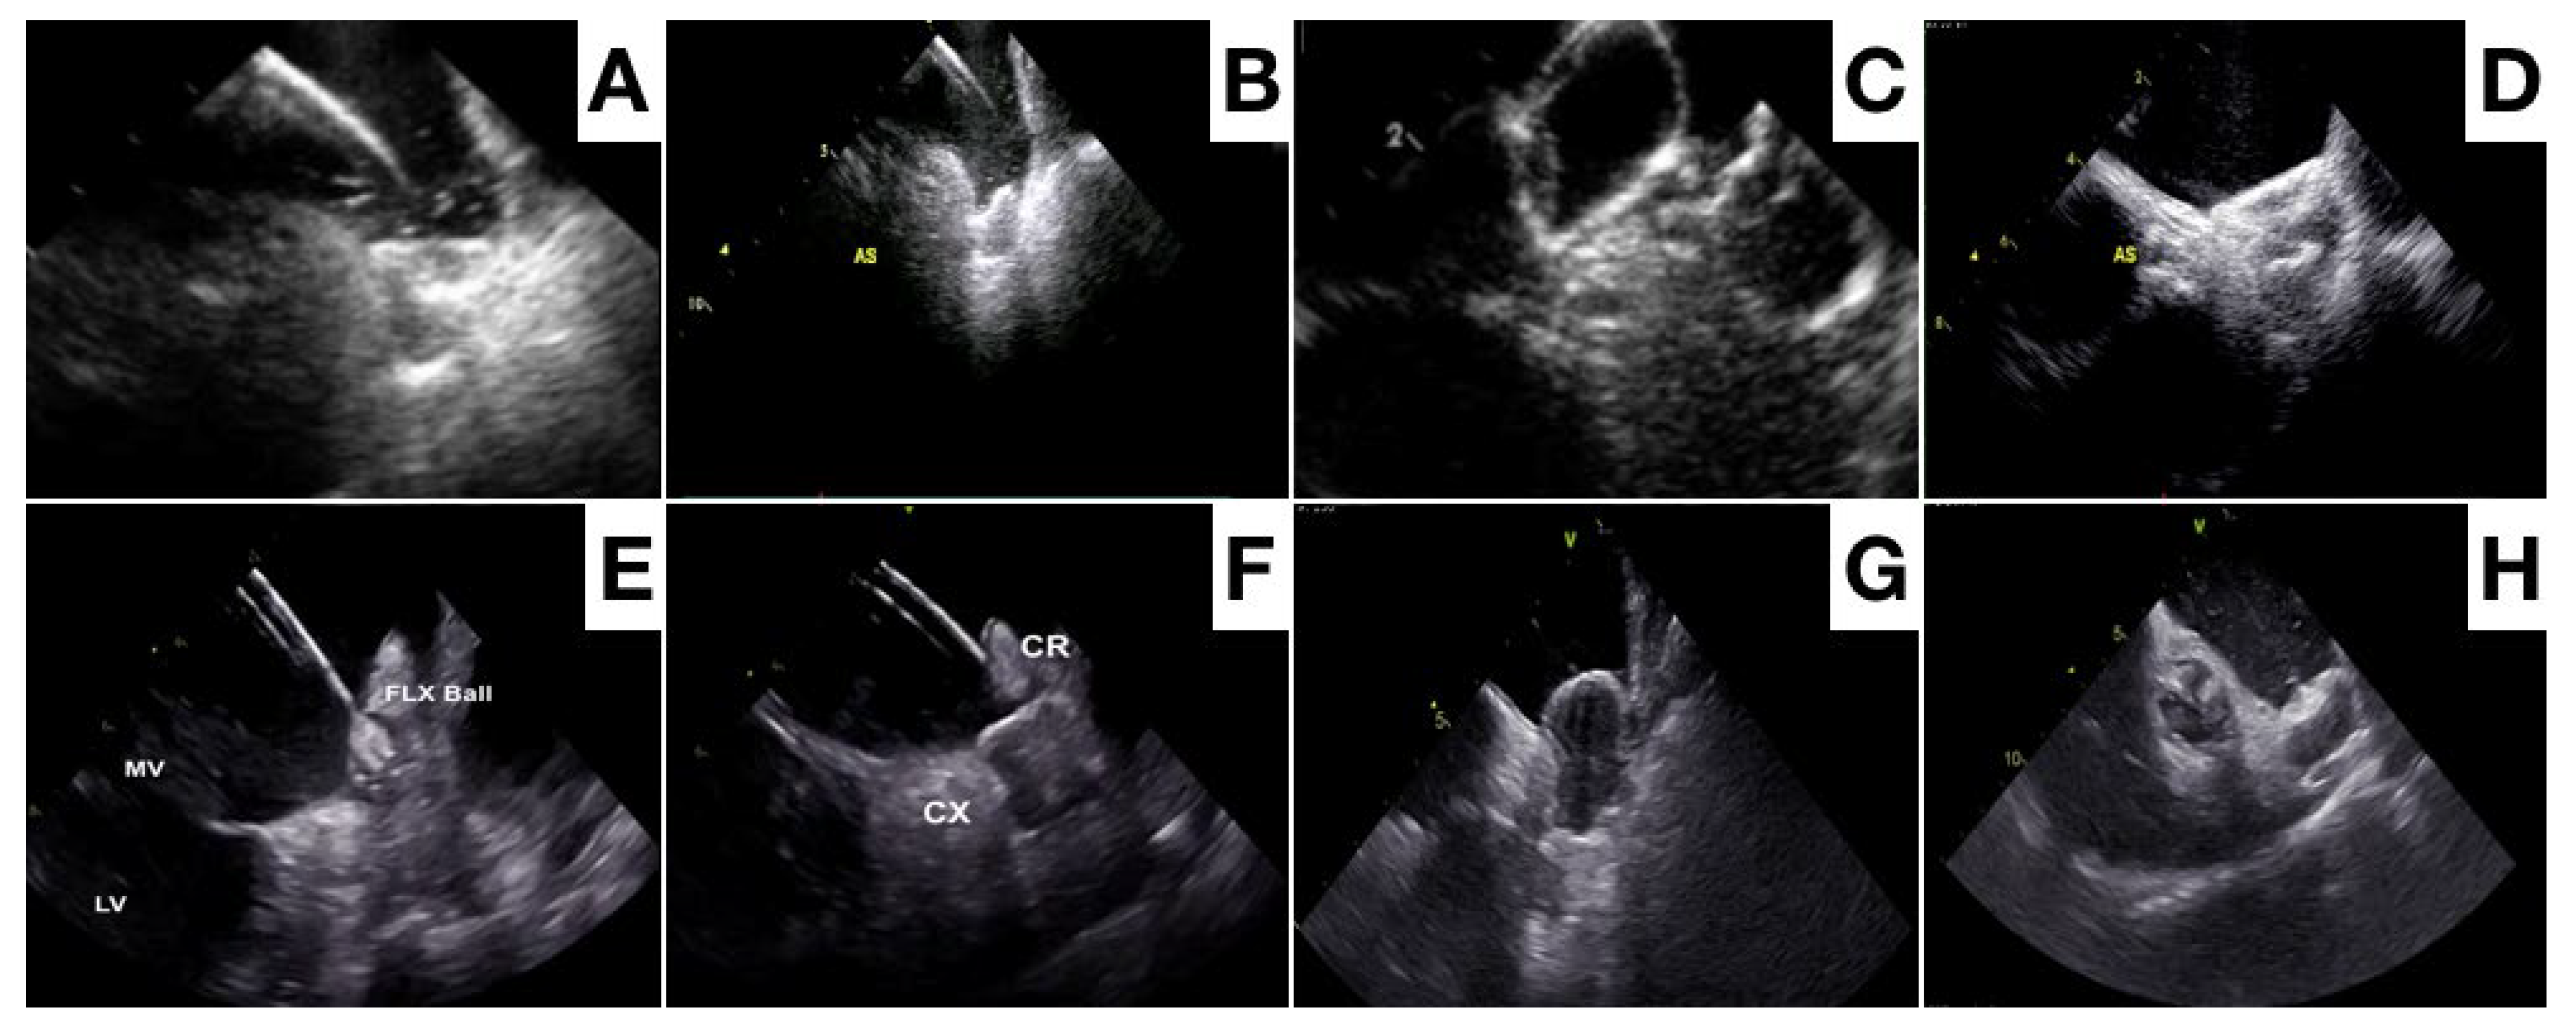

- Price, M.J.; Friedman, D.J.; Du, C.; Wang, Y.; Lin, Z.; Curtis, J.P.; Freeman, J.V. Comparative Safety of Transcatheter LAAO With the First-Generation Watchman and Next-Generation Watchman FLX Devices. J. Am. Coll. Cardiovasc. Interv. 2022, 15, 2115–2123. [Google Scholar] [CrossRef] [PubMed]

- Kar, S.; Doshi, S.K.; Sadhu, A.; Horton, R.; Osorio, J.; Ellis, C.; Stone, J., Jr.; Shah, M.; Dukkipati, S.R.; Adler, S.; et al. PrimaryOutcome Evaluation of a Next-Generation Left AtrialAppendageClosure Device: Results From the PINNACLE FLX Trial. Circulation 2021, 143, 1754–1762. [Google Scholar] [CrossRef]

- Saliba, W.I.; Kawai, K.; Sato, Y.; Kopesky, E.; Cheng, Q.; Ghosh, S.K.B.; Herbst, T.J.; Kawakami, R.; Konishi, T.; Virmani, R.; et al. Enhanced Thromboresistance and Endothelialization of a Novel Fluoropolymer-Coated Left Atrial Appendage Closure Device. JACC Clin. Electrophysiol. 2023, 9, 1555–1567. [Google Scholar] [CrossRef]

- Freeman, J.V.; Varosy, P.; Price, M.J.; Slotwiner, D.; Kusumoto, F.M.; Rammohan, C.; Kavinsky, C.J.; Turi, Z.G.; Akar, J.; Koutras, C.; et al. The NCDR Left AtrialAppendageOcclusionRegistry. J. Am. Coll. Cardiol. 2020, 75, 1503–1518. [Google Scholar] [CrossRef]

- Asmarats, L.; Rodes-Cabau, J. Percutaneous left atrial appendage closure: Current devices and clinical outcomes. Circ. Cardiovasc. Interv. 2017, 10, e005359. [Google Scholar] [CrossRef]

- Lakkireddy, D.; Thaler, D.; Ellis, C.R.; Swarup, V.; Sondergaard, L.; Carroll, J.; Gold, M.R.; Hermiller, J.; Diener, H.C.; Schmidt, B.; et al. Amplatzer amulet left atrial appendage occluder versus Watchman device for stroke prophylaxis (Amulet IDE): A randomized, controlled trial. Circulation 2021, 144, 1543–1552. [Google Scholar] [CrossRef]

- Galea, R.; De Marco, F.; Meneveau, N.; Aminian, A.; Anselme, F.; Gräni, C.; Huber, A.T.; Teiger, E.; Iriart, X.; Babongo Bosombo, F.; et al. Amulet or Watchman device for percutaneous left atrial appendage closure: Primary results of the SWISS-APERO randomized clinical trial. Circulation 2022, 145, 724–738. [Google Scholar] [CrossRef] [PubMed]

- Pivato, C.A.; Liccardo, G.; Sanz-Sanchez, J.; Pelloni, E.; Pujdak, K.; Xuareb, R.G.; Cruz-Gonzalez, I.; Pisano, F.; Scotti, A.; Tarantini, G.; et al. Left atrial appendage closure with the II generation Ultraseal device: An international registry. The LIGATE study. Catheter. Cardiovasc. Interv. 2022, 100, 620–627. [Google Scholar] [CrossRef] [PubMed]

- Wilkins, B.; Srimahachota, S.; De Backer, O.; Boonyartavej, S.; Lertsuwunseri, V.; Tumkosit, M.; Søndergaard, L. First-in-human results of the Omega leftatrialappendage occluder for patients with non-valvularatrialfibrillation. EuroIntervention 2021, 17, e376–e379. [Google Scholar] [CrossRef] [PubMed]

- Chow, D.H.F.; Wong, Y.H.; Park, J.W.; Lam, Y.Y.; De Potter, T.; Rodés-Cabau, J.; Asmarats, L.; Sandri, M.; Sideris, E.; McCaw, T.; et al. An overview of current and emerging devices for percutaneous left atrial appendage closure. Trends Cardiovasc. Med. 2019, 29, 228–236. [Google Scholar] [CrossRef]

- De Backer, O.; Hafiz, H.; Fabre, A.; Lertsapcharoen, P.; Srimahachota, S.; Foley, D.; Sondergaard, L. State-of-the-art preclinical testing of the OMEGATM leftatrialappendage occluder. Catheter. Cardiovasc. Interv. 2021, 97, E1011–E1018. [Google Scholar] [CrossRef]

- Huang, H.; Liu, Y.; Xu, Y.; Wang, Z.; Li, Y.; Cao, K.; Zhang, S.; Yang, Y.; Yang, X.; Huang, D.; et al. Percutaneous left atrial appendage closure with the LAmbre device for stroke prevention in atrial fibrillation: A prospective, multicenter clinical study. JACC Cardiovasc. Interv. 2017, 10, 2188–2194. [Google Scholar] [CrossRef]

- Sommer, R.J.; Lamport, R.; Melanson, D.; Devellian, C.; Levine, A.; Cain, C.M.; Kaplan, A.V.; Gray, W.A. Preclinical assessment of a novel conformable foam-based left atrial appendage closure device. Biomed. Res. Int. 2021, 2021, 4556400. [Google Scholar] [CrossRef]

- Sommer, R.J.; Kim, J.H.; Szerlip, M.; Chandhok, S.; Sugeng, L.; Cain, C.; Kaplan, A.V.; Gray, W.A. Conformal Left Atrial Appendage Seal Device for Left Atrial Appendage Closure. J. Am. Coll. CardiolIntv. 2021, 14, 2368–2374. [Google Scholar] [CrossRef]

- Wong, G.X.; Kar, S.; Smith, T.W.; Spangler, T.; Bolling, S.F.; Rogers, J.H. Transcatheter Left Atrial Appendage Exclusion: Preclinical and Early Clinical Results With the Laminar Device. J. Am. Coll. Cardiol. Interv. 2023, 16, 1347–1357. [Google Scholar] [CrossRef]

- Bavishi, C. Transcatheter Left Atrial Appendage Closure: Devices Available, Pitfalls, Advantages, and Future Directions. US Cardiol. Rev. 2023, 17, e05. [Google Scholar] [CrossRef]